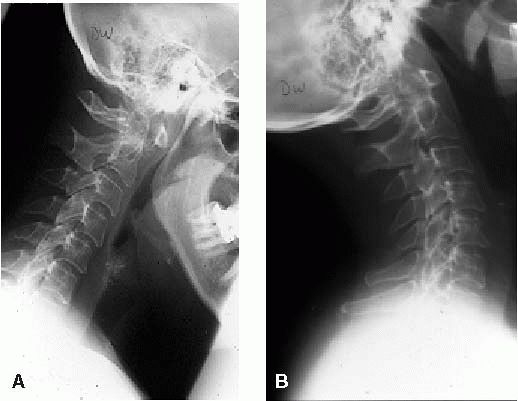

subluxation or C1-C2 rotatory displacement (rotatory subluxation of

childhood; Figure 11-2).

FIGURE 11-2.

Rotatory subluxation, C1 on C2. This open mouth view is consistent with atlantoaxial rotatory subluxation. There is tilt of the skull as well as a shift of the lateral masses of C1 on C2, with overlap of the lateral mass of C1 on C2 on the left side. Cineradiography or dynamic CT scan is the best method to confirm fixed rotatory subluxation of C1 on C2. |